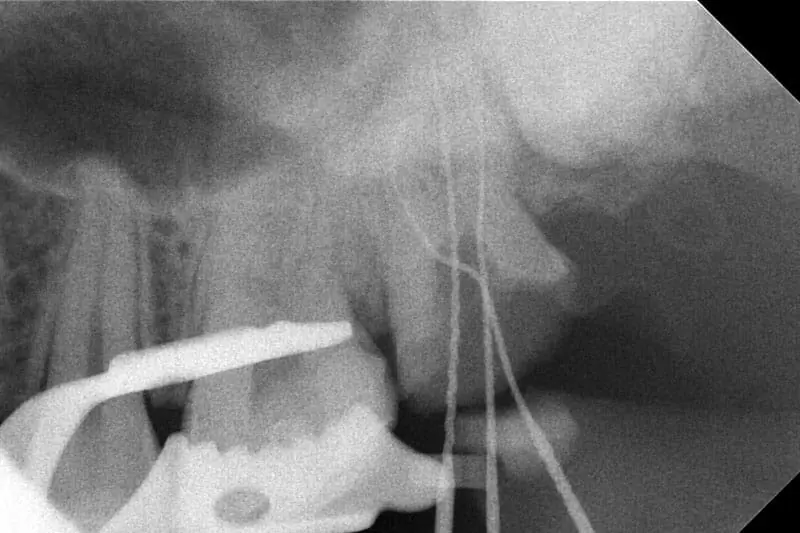

治療中X光片 (插針照)

療程開始讓我相當驚艷,沈醫師麻藥打的很無感,而且治療期間可以感受到醫師手法俐落,別於先前看診的經驗,最深得我心的就是醫師及助理間的默契,醫師簡短的口令,助理不慌不忙的遞上醫師需求,這相當不容易,因為先前多次看診經驗,助理常常不知道醫師的下個步驟,整個治療過程都在聽助理被醫師"叮嚀",非常影響看診情緒...所以這部分充分反映敦南麗緻助理訓練有素!根管完成後,沈醫師先觀察並裝臨時牙套保護,確定根管沒問題,才安排時間做假牙。而在這之間碰上意外的插曲,端午連假我的臨時牙套掉了,第一時間我與診所連繫,但因為連假出遊無法馬上回診,櫃檯小姐細細為我解說該注意的部分,並要我不用過於擔心,也會將我的狀況告知沈醫師,所以假期結束後回診,沈醫師很佛心的為我重做臨時牙套,而一週後我也完成假牙裝置。